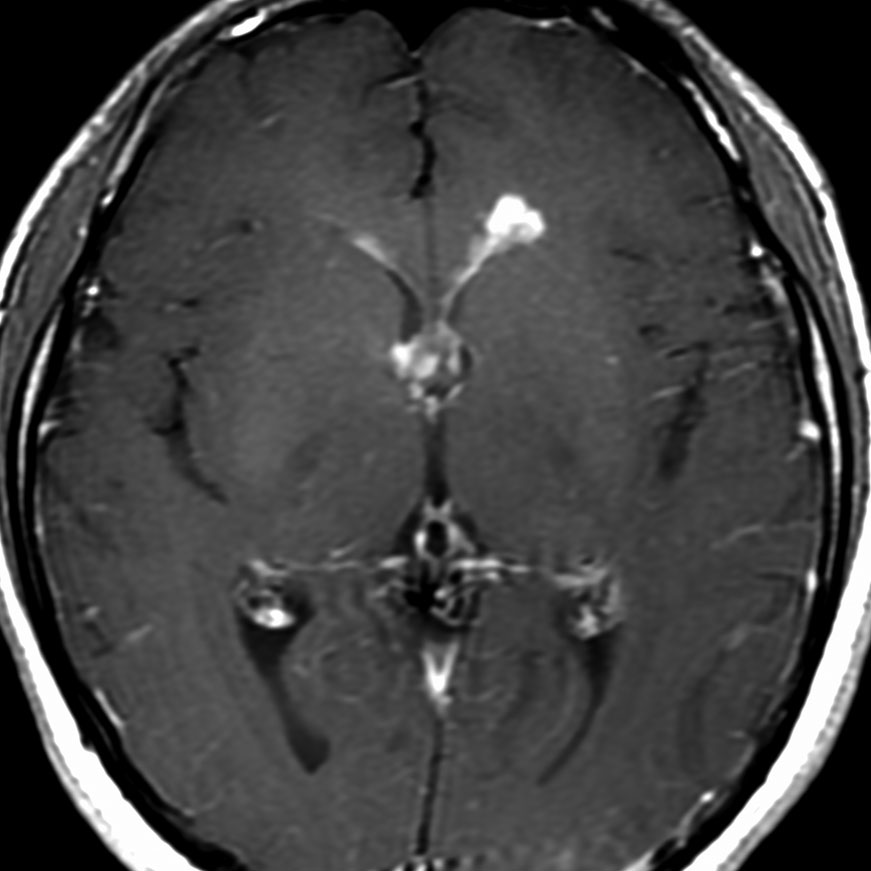

左はICE化学療法 (IFO/CDDP/VP-16)前,右は1コース終了後です。腫瘍は顕著に縮小してgerminomaとして普通の化学療法反応性を示します。また,松果体と下垂体には腫瘍はありません。

ICEを3コース行なって腫瘍は完全消失して,前頭葉浮腫も消えました。その後に,全脳照射 25.2Gy/14分割を加えました。無症状で復職することができました。